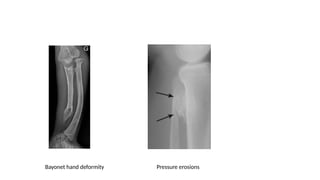

• Radiological features – Multiple osteochondromas, Bayonet hand

deformity, pressure erosions to adjacent bones

Bayonet hand deformity Pressure erosions